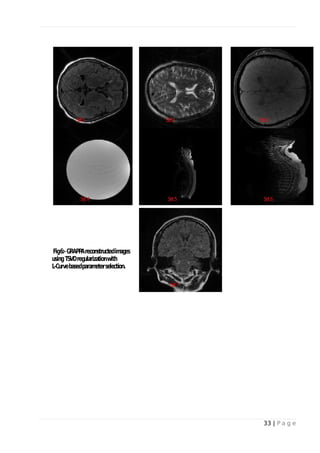

 L-curve method for selecting truncation parameter in TSVD:

Fig-1 and Fig-5 shows the plots of solution norm versus residual norm for data sets I to VII. The

circles indicate values of regularization parameter at each point on the L-curve. The optimum

parameter is at the corner of the L-curve. Dataset II and III shows sharp L-curve corner. Images

reconstructed using parameter chosen from L-curve corner are shown in Fig-2 and Fig-6.

Fig. 2: - GRAPPA reconstructed images using TSVD regularization with L-Curve based

parameter selection